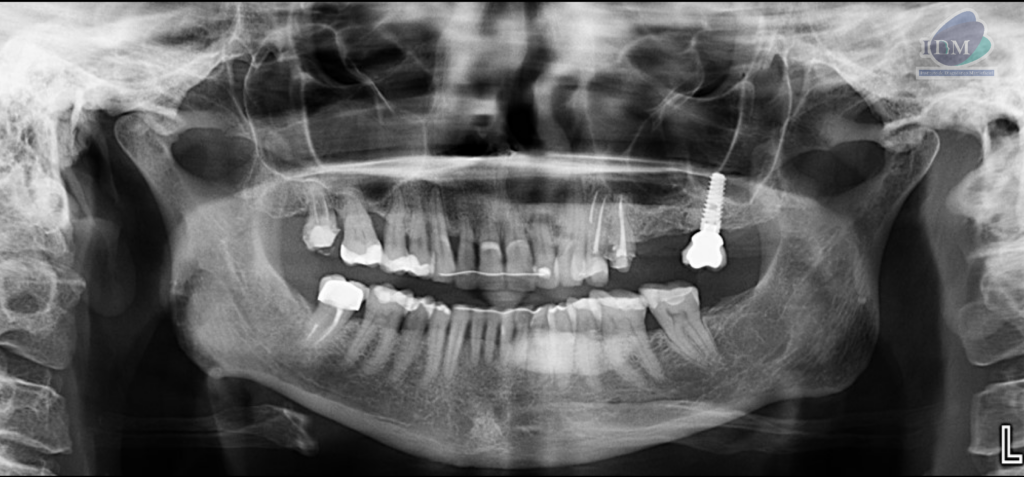

Paciente femenina de 65 años acude al centro para una tomografía de cráneo completo para una evaluación general. A la evaluación de la radiografía panorámica se observa aplanamiento y erosión del contorno condilar bilateral que ocasiona la presencia de osteofito en el cóndilo del lado derecho compatible con un proceso degenerativo articular. Asimismo, se observa la neumatización de ambos senos maxilares, la reabsorción ósea moderada del proceso alveolar, la presencia de dispositivo de ferulización en piezas anterosuperiores y anteroinferiores, múltiples restauraciones coronarias, tratamiento de conductos en las piezas 18 y 47, presencia de implante dental con corona protésica en zona de pieza 27. Finalmente se observa una imagen radiopaca difusa de forma irregular que se proyecta en cuerpo mandibular del lado izquierdo sobre la porción radicular de la pieza 32 hasta la pieza 36.

Radiografia Panorámica